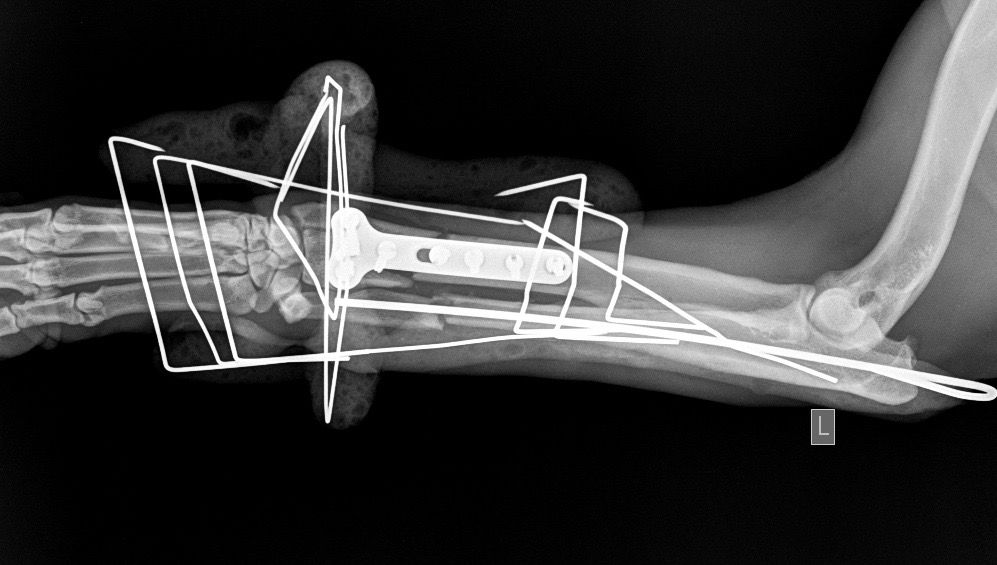

LeilaGnomatefsiKtiniatroΗ γνωμάτευση του κτηνίατρου που έκανε το ορθοπεδικό χειρουργείο.

Η κα Μακρή δημοσίευσε σήμερα στο facebook την γνωμάτευση του κτηνιάτρου σχετικά με την εξέλιξη της υγείας του ζώου. Σε αυτή αναφέρεται ότι: «Ο σκύλος έφερε συντριπτικά ενδοαρθρικά κατάγματα με μετατόπιση στο κάτω τρίτο του αριστερού αντιβραχίου και στο κάτω τρίτο του αριστερού μηριαίου. Ολοκληρώθηκε με επιτυχία η πρώτη χειρουργική επέμβαση που αφορούσε την ανάταξη και οστεοσύνθεση του αριστερού αντιβραχίου. Λόγω της σοβαρότητας του κατάγματος η διάρκεια της χειρουργικής επέμβασης ήταν 4 ώρες και 25 λεπτά και ο σκύλος ανένηψε φυσιολογικά».